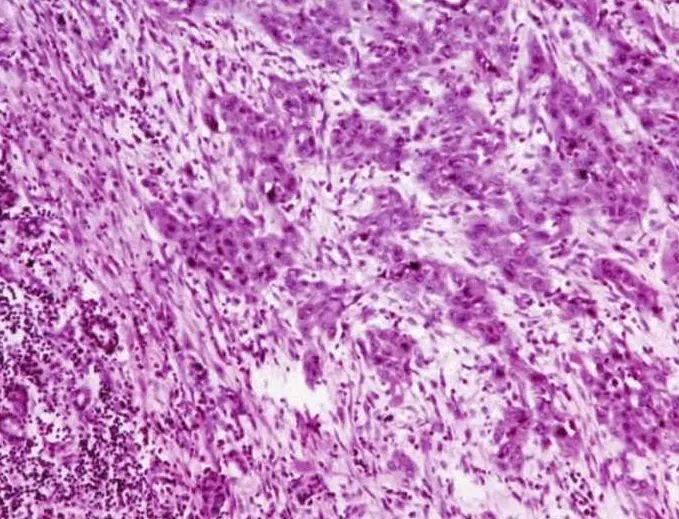

的有关信息介绍如下:概述唾液腺鳞状细胞癌(squamous cell carcinoma,SCC)又称表皮样癌,是指原发于唾液腺的鳞状细胞癌,极为少见。国内上海的6982例唾液腺肿瘤研究中,发生在大唾液腺者为5002例,其中恶性1008例,包括鳞状细胞癌鳞癌36例(占大唾液腺肿瘤0.7%;占大唾液腺癌3.6%),其中腮腺29例、下颌下腺7例。国内7所口腔医学院校36944例唾液腺肿瘤中有原发性鳞状细胞癌102例,占0.3%。其组织发生可来源于排泄管的基底细胞或唾液腺导管的鳞状化生。病因因素可能与辐射暴露相关。唾液腺原发性鳞状细胞癌是排除性诊断,即诊断前首先应排除来自于上面部皮肤、外听道、头皮和有时包括上呼吸消化道的转移性癌。也应排除外听道和皮肤鳞状细胞癌的直接扩展,还要排除其他腮腺肿瘤如高级别黏液表皮样癌、有鳞状分化的唾液腺导管癌(还包括多形性腺瘤恶变为鳞状细胞癌者)。对于下下颌下腺的原发性鳞状细胞癌应首先排除口底鳞状细胞癌的直接扩散,此部位转移性癌罕见。由于报道上的偏差和数据结构的不同,从文献上很难得到原发性大唾液腺鳞状细胞癌的发病率。多数文献包括了转移性和其他部位浸润至腺体的鳞状细胞癌,因此不同文献报道的发病率差异很大。临床表现此瘤主要发生于腮腺和下颌下腺,腮腺多见。罕见情况下鳞状细胞癌可来自于Stensens管或舌下腺。小唾液腺偶尔也发生鳞状细胞癌,但由于很容易与口腔黏膜癌混淆,难以确定。男性较多见,且多见于中年以上,50~70岁为发病高峰。肿物生长较快,病期短,多在半年以内,无症状或伴有疼痛。腮腺肿瘤多出现面瘫,皮肤表面可出现溃疡,浸润性生长,边界不清,与皮肤和/深部软组织固定。常发生区域淋巴结转移。X线唾液腺造影显示导管中断,腺泡充盈缺乏,碘油外溢。在腭部者X线片可见溶骨性破坏、界限不清的肿块。发生在唾液腺导管处的肿瘤由于部分或全部阻塞导管,可导致腮腺间断性疼痛性腮腺肿大,类似于炎症表现。临床上可误诊。大体病理肉眼见肿瘤形态不规则,多大于3cm、质地较硬,无包膜,与周围组织无界限。剖面实质性,灰白色,易碎。临床表现此瘤主要发生于腮腺和下颌下腺,腮腺多见。罕见情况下鳞状细胞癌可来自于Stensen's管或舌下腺。小唾液腺偶尔也发生鳞状细胞癌,但由于很容易与口腔黏膜癌混淆,难以确定。男性较多见,且多见于中年以上,50~70岁为发病高峰。肿物生长较快,病期短,多在半年以内,无症状或伴有疼痛。腮腺肿瘤多出现面瘫,皮肤表面可出现溃疡,浸润性生长,边界不清,与皮肤和/深部软组织固定。常发生区域淋巴结转移。X线唾液腺造影显示导管中断,腺泡充盈缺乏,碘油外溢。在腭部者X线片可见溶骨性破坏、界限不清的肿块。发生在唾液腺导管处的肿瘤由于部分或全部阻塞导管,可导致腮腺间断性疼痛性腮腺肿大,类似于炎症表现。临床上可误诊。大体病理肉眼见肿瘤形态不规则,多大于3cm、质地较硬,无包膜,与周围组织无界限。剖面实质性,灰白色,易碎。组织病理镜下表现与黏膜上皮发生的鳞状细胞癌相同。有时可见唾液腺导管的原位癌样的改变(图7-276)。浸润癌为增生的鳞状上皮团块,细胞大小不等,有核浓染及核分裂像,有的细胞巢可见角化珠或细胞间桥,根据细胞的分化程度,可分为高、中及低度分化(图7-277、7-278)。多为有角化的、分化较高的鳞状细胞癌,低分化者不到10%。有时可见原位导管异常增生,这种表现有助于原发性鳞状细胞癌诊断的确立。

图7-277 鳞状细胞癌:肿瘤细胞团中央的坏死

图7-278 鳞状细胞癌:肿瘤细胞呈小巢状浸润细胞遗传学研究较少,结果不一。有6q缺失的报道(许多其他唾液腺肿瘤也有),但在头颈部其他部位的鳞状细胞癌少见。鉴别诊断1、转移性鳞状细胞癌:鳞状细胞癌转移至唾液腺者较原发性者多得多,临床病史及仔细的临床检查有助于排除头皮和皮肤的鳞状细胞癌转移。2、低分化黏液表皮样癌:足够的取材可能发现较典型的黏液细胞分化区域。细胞内黏液染色阳性可确定黏液表皮样癌的诊断。3、坏死性唾液腺化生:以腭部最常见,腺小叶坏死,泡壁溶解消失,有黏液外溢,腺导管上皮鳞状化生,形成上皮岛。鳞状细胞分化较好,不存在细胞异型性或间变。4、角化囊性瘤(keratocystoma):是最近描述的唾液腺罕见的病变,可能与鳞状细胞癌混淆。该瘤的特点是多囊性腔隙,衬覆复层鳞状上皮,含角质板片和局部上皮岛。此瘤不发生转移、无坏死或浸润以及无细胞学的非典型性,细胞增殖活性低是与原发性鳞状细胞癌鉴别的主要依据。5、罕见情况下,鳞状细胞癌可能可能是多形性腺瘤恶变的癌成分,或者是Warthin瘤恶变的癌成分,充分取材可以做出正确诊断。6、淋巴上皮癌:有独特的非角化不成熟的表现,并且有丰富的淋巴样间质,容易与鳞状细胞癌区别。预后鳞状细胞癌为高度恶性肿瘤,常发生颈部淋巴结转移,预后较差,患者多在两年内死亡。